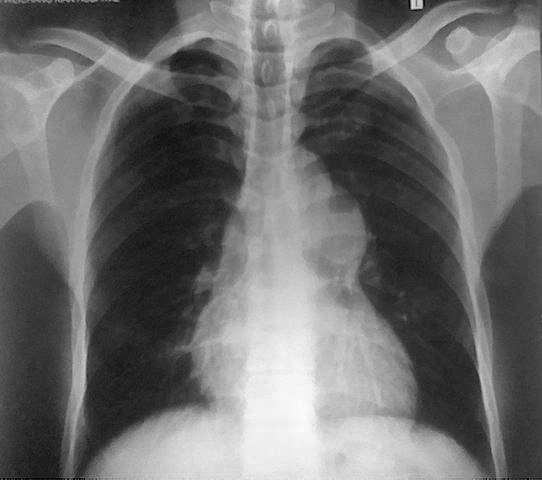

可符合肺动脉狭窄后扩张。

依据:

1.两肺纹理稀少,肺透亮度增高。(肺血减少)

2.心影增大,呈“梨形”;心尖圆钝,右心缘下段向右扩大(说明以右心室增大为主);肺动脉段膨隆。

1、两肺纹理稀疏,肺叶透亮度增强。

2、肺动脉段显著膨隆,心影不大。

考虑:肺动脉狭窄?肺动脉瘤?